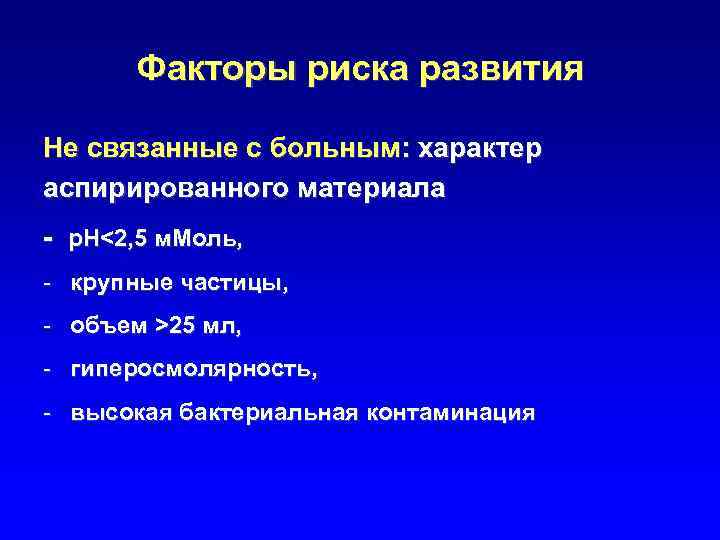

Факторы риска развития Не связанные с больным: характер аспирированного материала - p. H<2, 5 м. Моль, - крупные частицы, - объем >25 мл, - гиперосмолярность, - высокая бактериальная контаминация